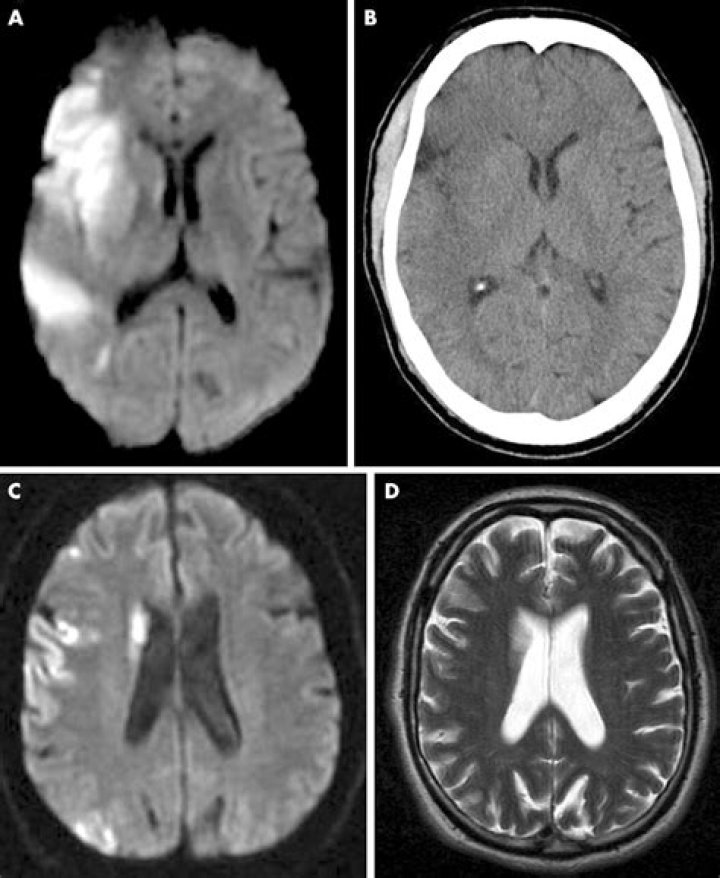

Brain magnetic resonance imaging (MRI) is the preferred and most sensitive modality after transient ischemic attack (TIA) or minor stroke. It should include diffusion-weighted imaging (DWI) and should be completed within 24 hours of symptom onset1,2; its use is 3-fold.

MRIs can detect tissue damage even when symptoms are temporary. The sophisticated imaging technique can detect stroke lesions that may become less apparent quickly. A study from the journal Stroke followed 263 patients who had suffered a TIA or minor stroke and received a baseline MRI within 24 hours.